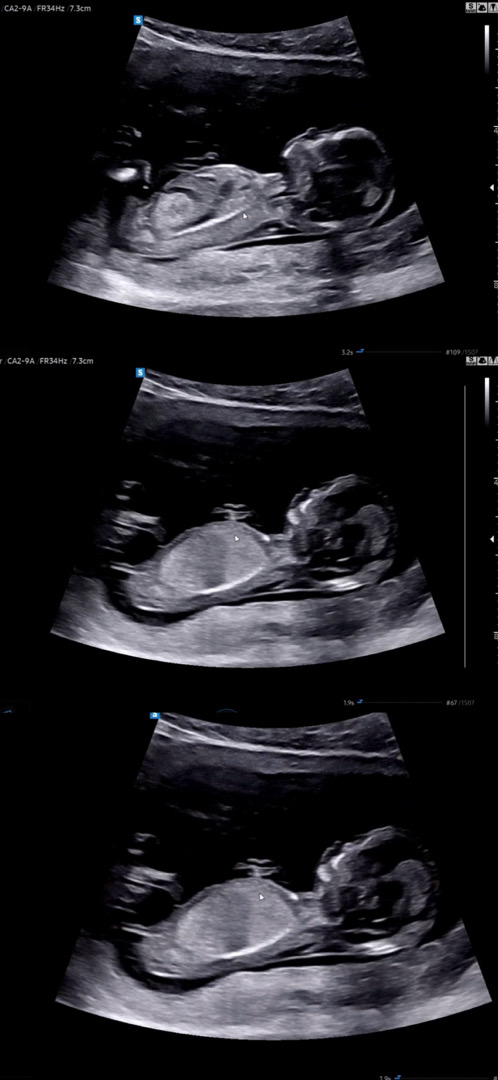

각도법 한번만 봐주세요!12주 4일입니다😣

각도법 한번만 봐주세요! 12주 4일입니다😣 감사합니다~